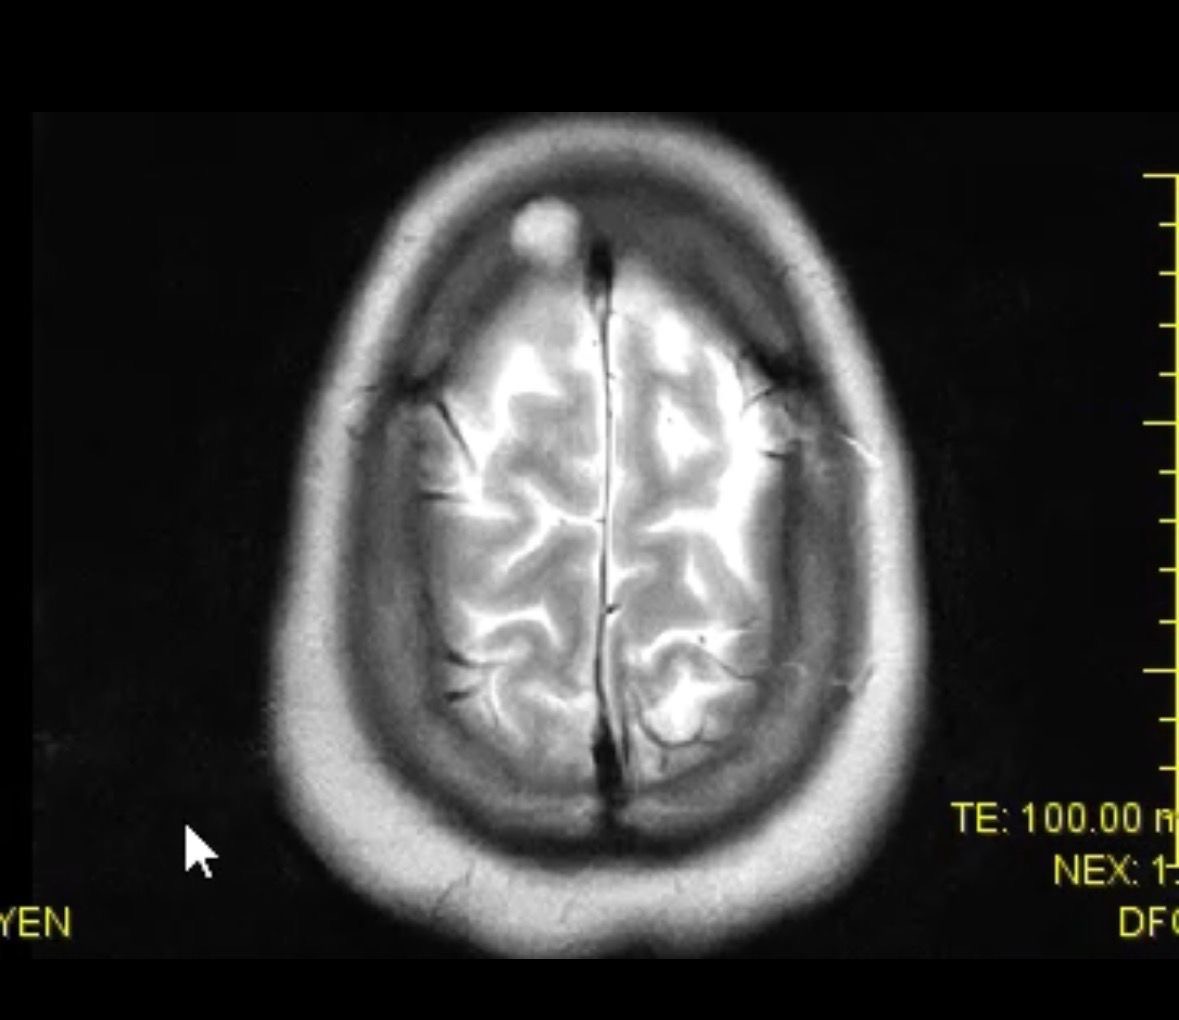

After a brain scan, we learned that there are not one, but two lesions near his brain. In that moment, everything shifted.

Right now, doctors believe the masses have not penetrated the brain itself and are treating him with curative intent. Our next steps include a PET scan and a kidney biopsy at St. Luke’s in the Houston Medical Center, followed by immunotherapy.